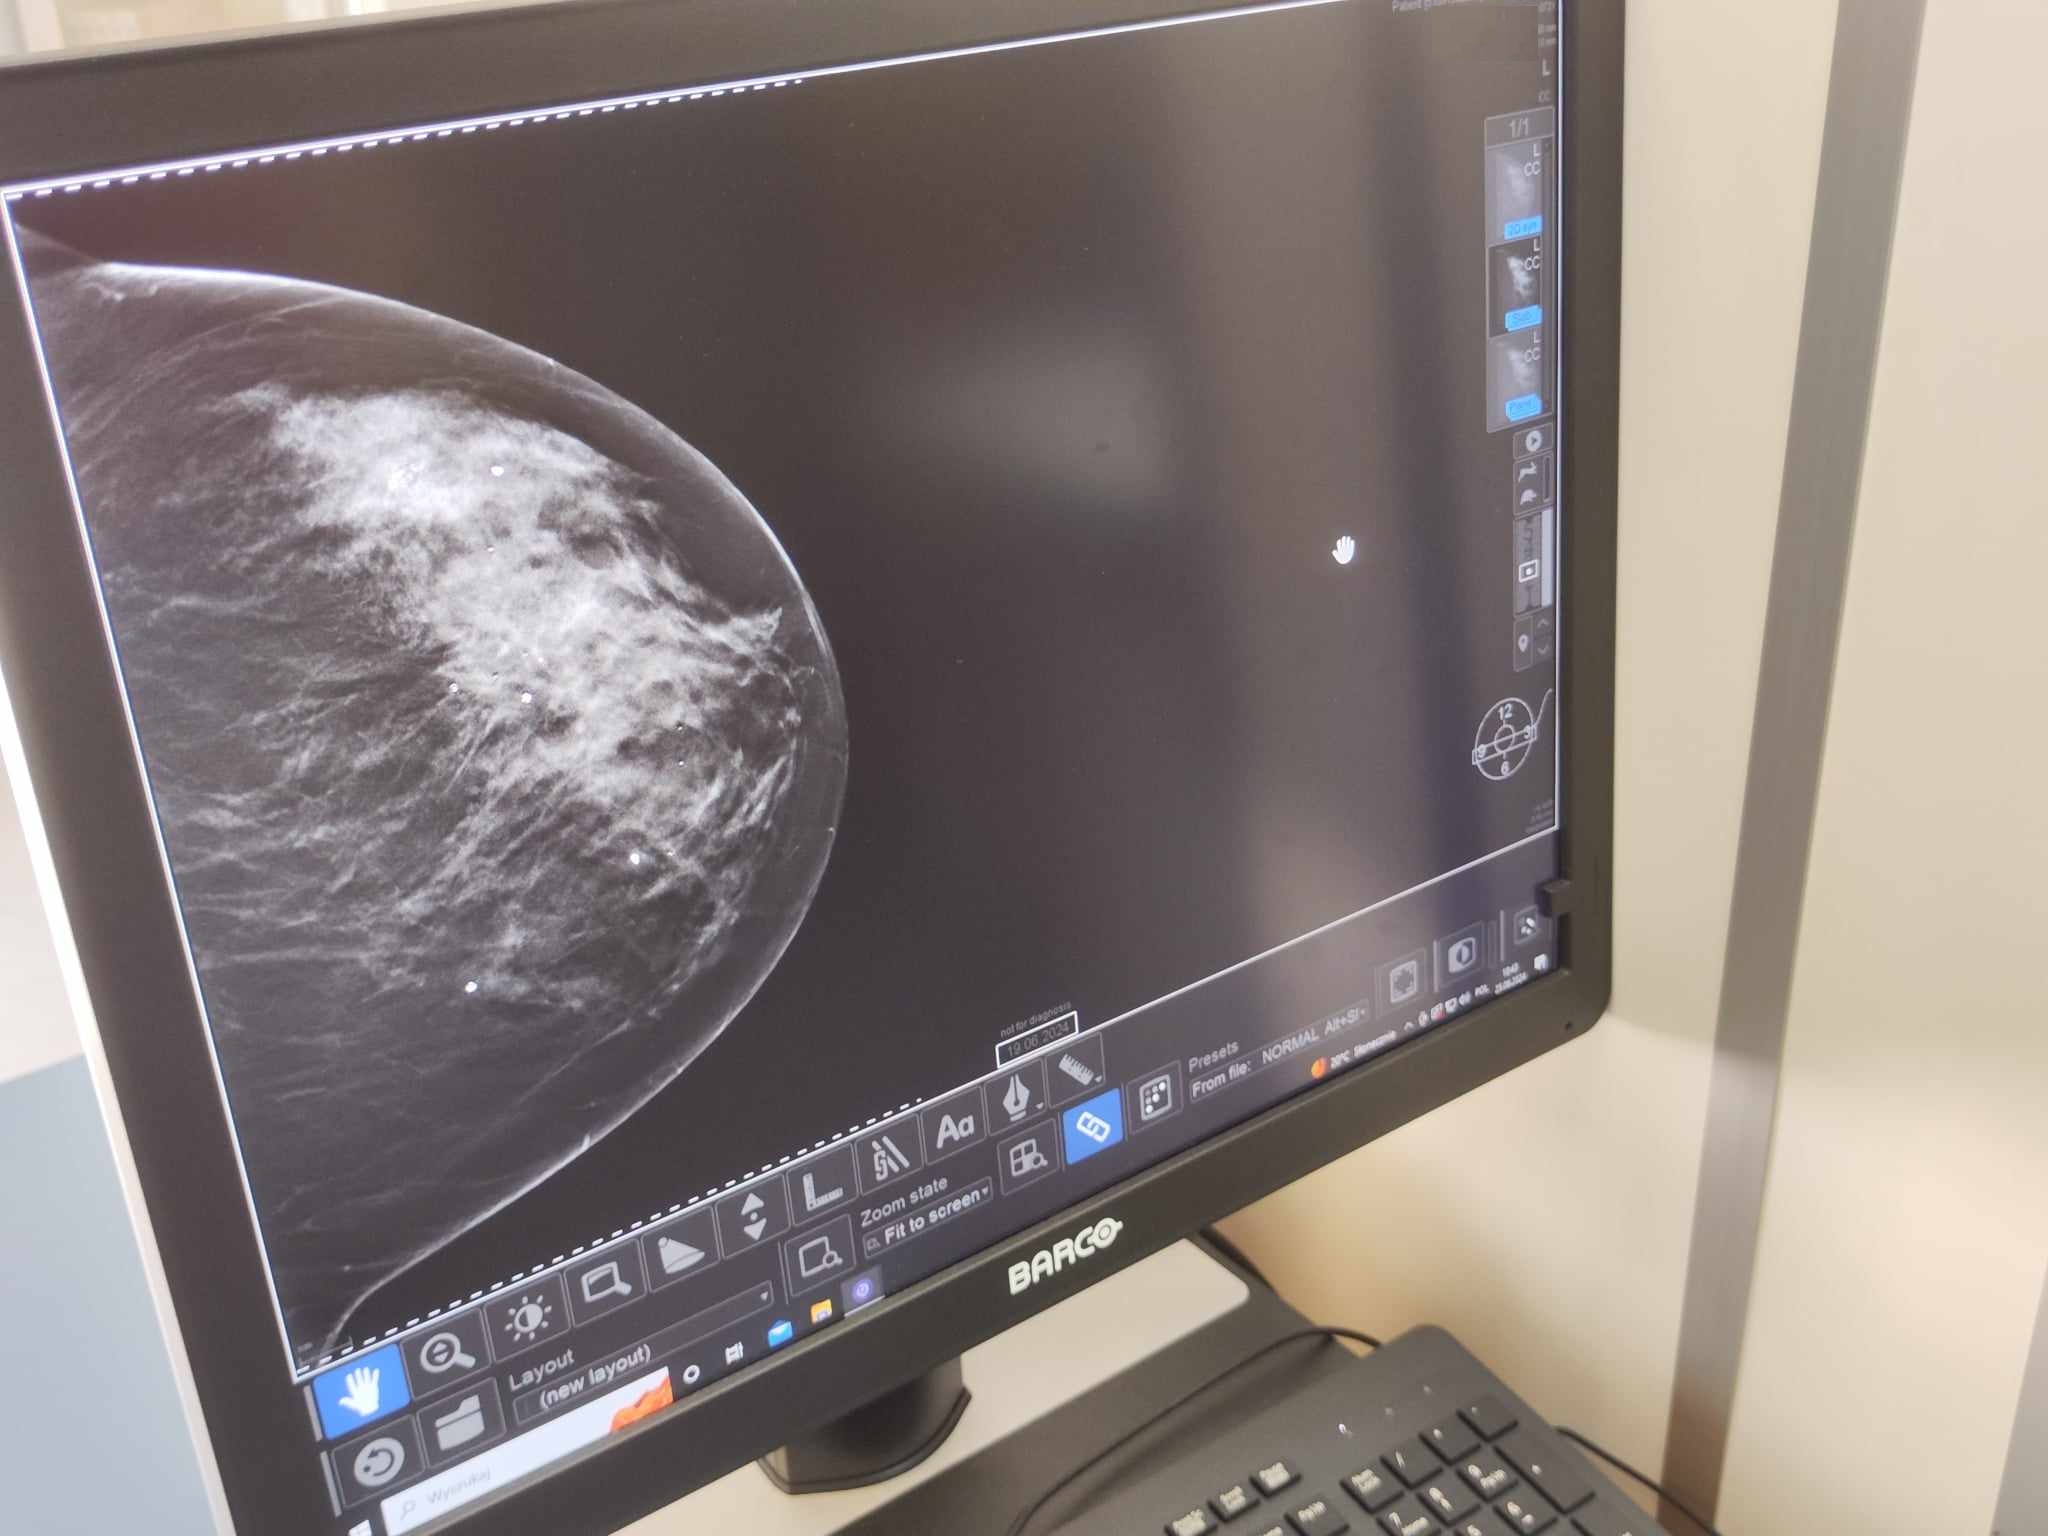

– Tomosynteza jest technologią uzupełniającą standardowe badanie mammograficzne. Pozwala na uzyskanie dokładniejszych obrazów, zatem ułatwia rozpoznawanie chorób piersi. Badanie standardowe obrazuje strukturę gruczołu piersiowego w sposób płaski, co utrudnia rozpoznanie zmian chorobowych. Tomosynteza eliminuje ten problem, wykonując zdjęcia warstwowe gruczołu piersiowego – wyjaśnia Elżbieta Soszyńska, specjalista radiolog.

Badanie tomosyntezy wygląda podobnie do standardowego badania mammograficznego, jednak jest krótsze i bardziej precyzyjne, ponieważ bada tylko tę część piersi, na której zauważono zmiany wymagające oceny.